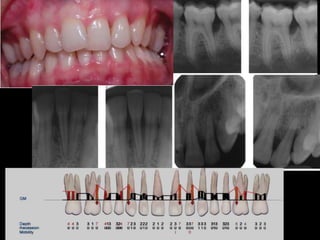

Este documento presenta información sobre periodontitis agresivas. Brevemente resume que la periodontitis agresivas se caracteriza por una destrucción periodontal rápida y severa en personas mayormente jóvenes y sanas. Menciona que la causa principal es la presencia de bacterias patógenas como Aggregatibacter actinomycetemcomitans. Finalmente, indica que tiene una mayor prevalencia en personas de raza caucásica, hispana y afroamericana en comparación con personas de raza china.